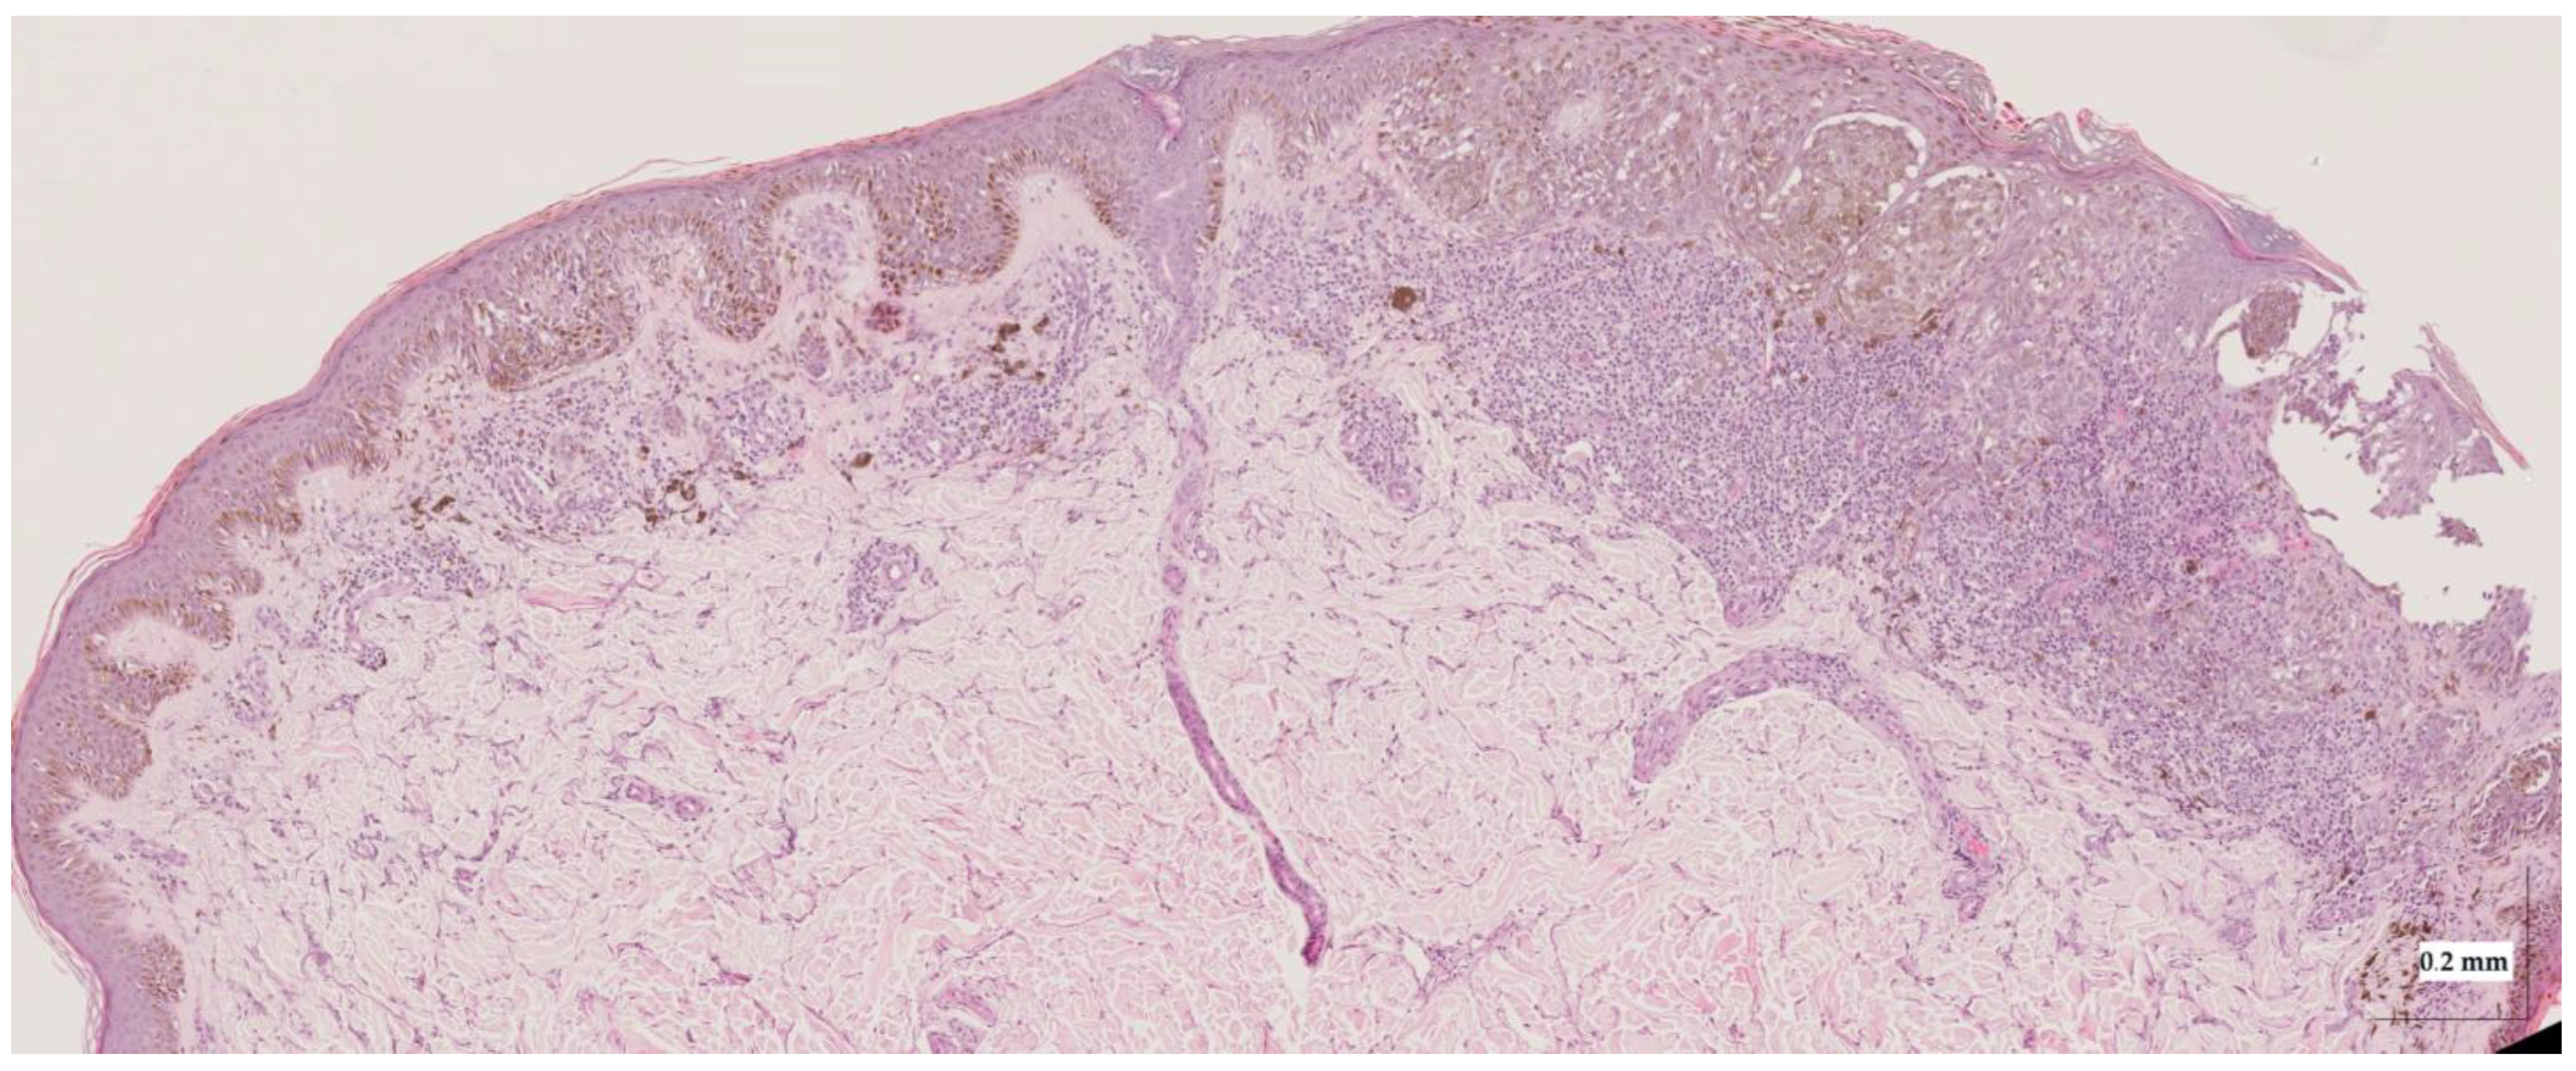

Appendix A. Selected Cases Studies’ HE Histopathological Images (Limited to OCT FOV)

| Superficial spreading melanoma (SSM) Case 2 | Localization: right forefoot (right ankle) |

![]() | ![]() |